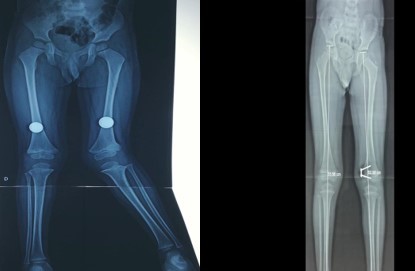

• Deformidades angulares de rodilla

• Discrepancias de longitud de miembros pélvicos

Rodillas en valgo

También llamadas rodillas valgas o rodillas en varo, estas condiciones se refieren a la alineación de las piernas. Estas alineaciones pueden ser un estado natural del desarrollo de un niño o una niña hasta los 7 años de edad. Después de esta edad, ya no se consideran normales. Sin embargo, en algunos casos, esta deformidad puede aumentar hasta llegar a ser discapacitante y dolorosa, y es en ese momento cuando debe ser tratada.

Consulta y desarrolo de nuestros pacientes despues de ser intervenidos, lo que muestra la evolucion y avances desde la primera vez que nos visitaron